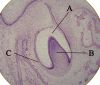

Tooth bud (labels) – histology slide10 views